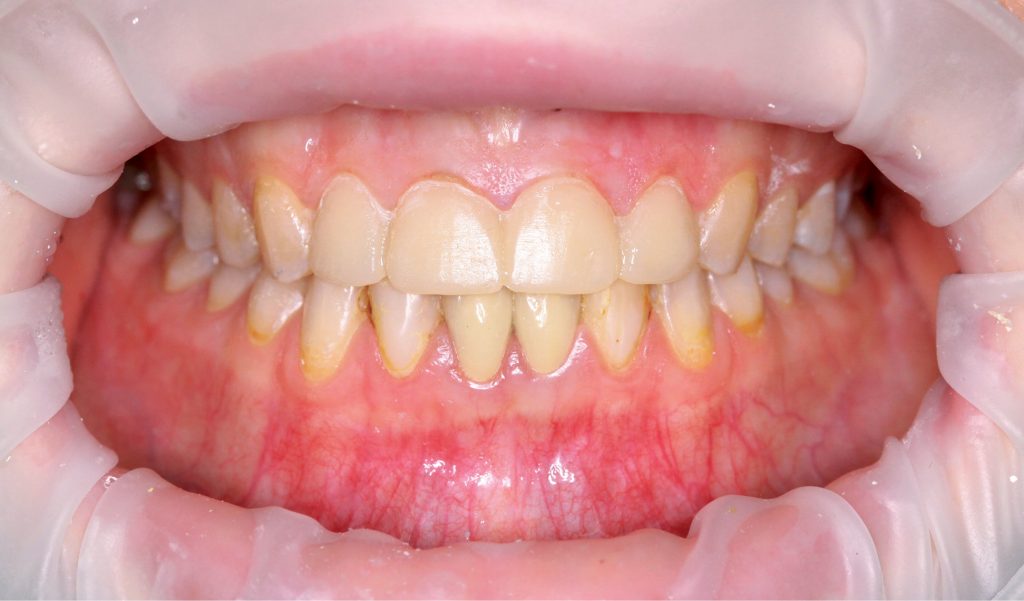

STRESZCZENIE: Poprawa estetyki uzębienia przy wykorzystaniu licówek jest obecnie często stosowana w praktyce lekarza dentysty. W pracy opisano przypadek 24-letniej pacjentki, która trafiła do gabinetu stomatologicznego w celu poprawy estetyki zębów siecznych szczęki. Opisano przebieg procesu przygotowania pacjentki do leczenia estetycznego przy użyciu licówek ceramicznych. Omówiono etapy oraz przedstawiono wyniki leczenia.

SUMMARY: Currently, improving the aesthetics of teeth using veneers is often used in the dental practice. This paper presents a case of a 24-year-old patient who was admitted to a dental office to improve the aesthetics of the maxillary incisors. The process of preparing the patient for an aesthetic treatment using ceramic veneers is described. The stages of the treatment are discussed and its results are presented.